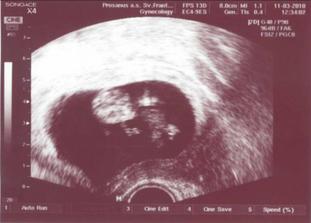

# 11.3. o 11.00 - Super poradňa. Hneď na privítanie mi vzali krv na screening a odovzdala som vzorku moču - negatívna. Doktorka ma privítala slovami:"Gaťky dolu!" Naše malé má 39mm, čo zodpovedá 10tt+6, podľa kalendára sme mali byť presne 11t, takže rastieme v norme 🙂 Na fotke vidno 4 fliačiky, čo by mali byť rúčky a nôžky. Všetko vyzerá byť v poriadku... až na výsledky posledných odberov, lebo mám zvýšené zápalové hodnoty, tak musím na druhý deň priniesť sterilnú vzorku moču na kultiváciu a vydržať do utorka alebo štvrtka na výsledky. Ak budú výsledky dobré, stretneme sa až na poradni 1.4.- P.S.: A už máme tehotenský preukaz!